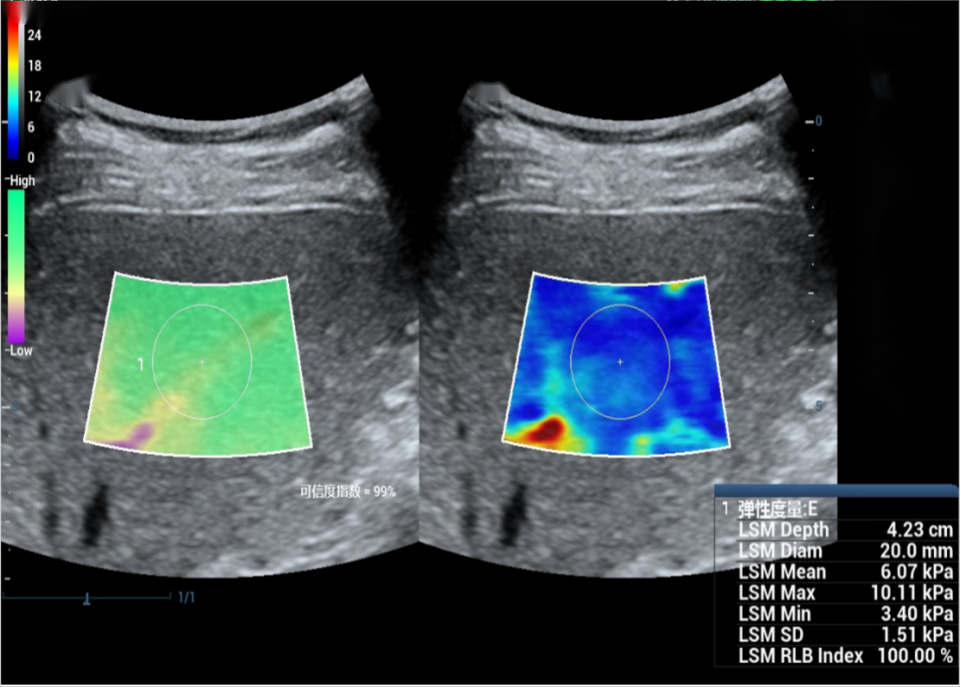

定量弹性成像

• 超星创新

SUPSTAR率先提出了将剪切波速测量与徒手弹性成像和声辐射力成像相融合的新型超声定量弹性成像技术。该技术是在定量测量组织局部区域的剪切波波速的基础上,根据不同区域剪切波波速的测量值,波速与组织杨氏模量之间的物理对应关系,以及不同成像模式之间的映射关系,实现定量的徒手弹性成像与声辐射力弹性成像。